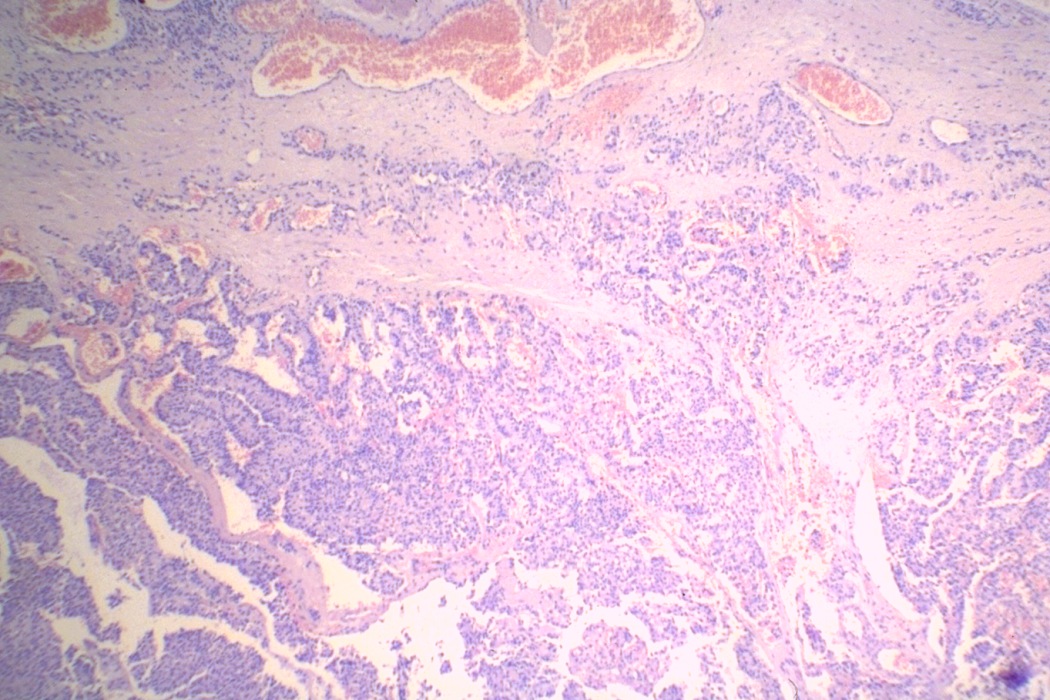

Thyroid cancers - case 1463 (histological picture 1)

H.E.-section, 40x. The tumor infiltrates the capsule of the thyroid.